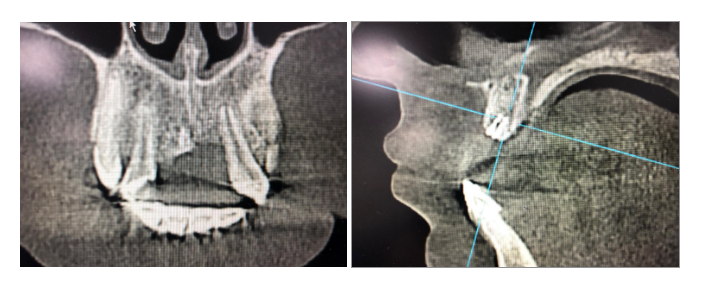

02.05.2024 сделана КЛКТ челюстей и пациент обратился в стоматологическую клинику «ЭТАЛОН» с целью восстановления целостности зубного ряда

Диагноз: хронический периодонтит зуба 1.1, анкилоз.